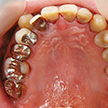

4. 初診時下顎

主訴である右下7番は早々に健康保険内インレー処置としました。下顎に関しては上顎のような問題は特になさそうです。しいて言えばテトラサイクリン等によると考えられる歯の変色でしょうか。